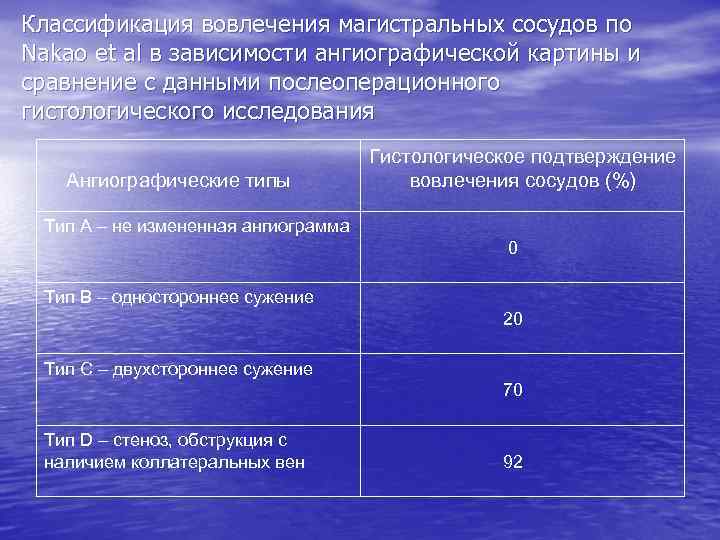

Классификация вовлечения магистральных сосудов по Nakao et al в зависимости ангиографической картины и сравнение с данными послеоперационного гистологического исследования Ангиографические типы Гистологическое подтверждение вовлечения сосудов (%) Тип А – не измененная ангиограмма 0 Тип В – одностороннее сужение 20 Тип С – двухстороннее сужение 70 Тип D – стеноз, обструкция с наличием коллатеральных вен 92